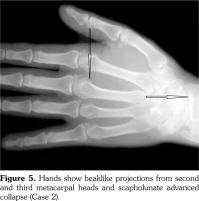

Case 2- A 39-year-old male patient presented with swelling of both knee joints. He also gave a history of recurrent painful swelling of knee joints and wrist joints for more than 10 years and was treated by an Ayurvedic physician. Other medical history or family history of medical problems were insignificant. There was a massive swelling of both knee joints with effusions, which was aspirated and the X-rays revealed calcification of the articular cartilages (Figure 5). A written informed consent was obtained from the patient.

His hand X-rays showed hook like projections arising from radial aspect of second and third metacarpal heads with scapholunate advanced collapse and indentation of distal radius by the scaphoid bone. It also showed CC of the triangular fibrocartilage (Figure 6).